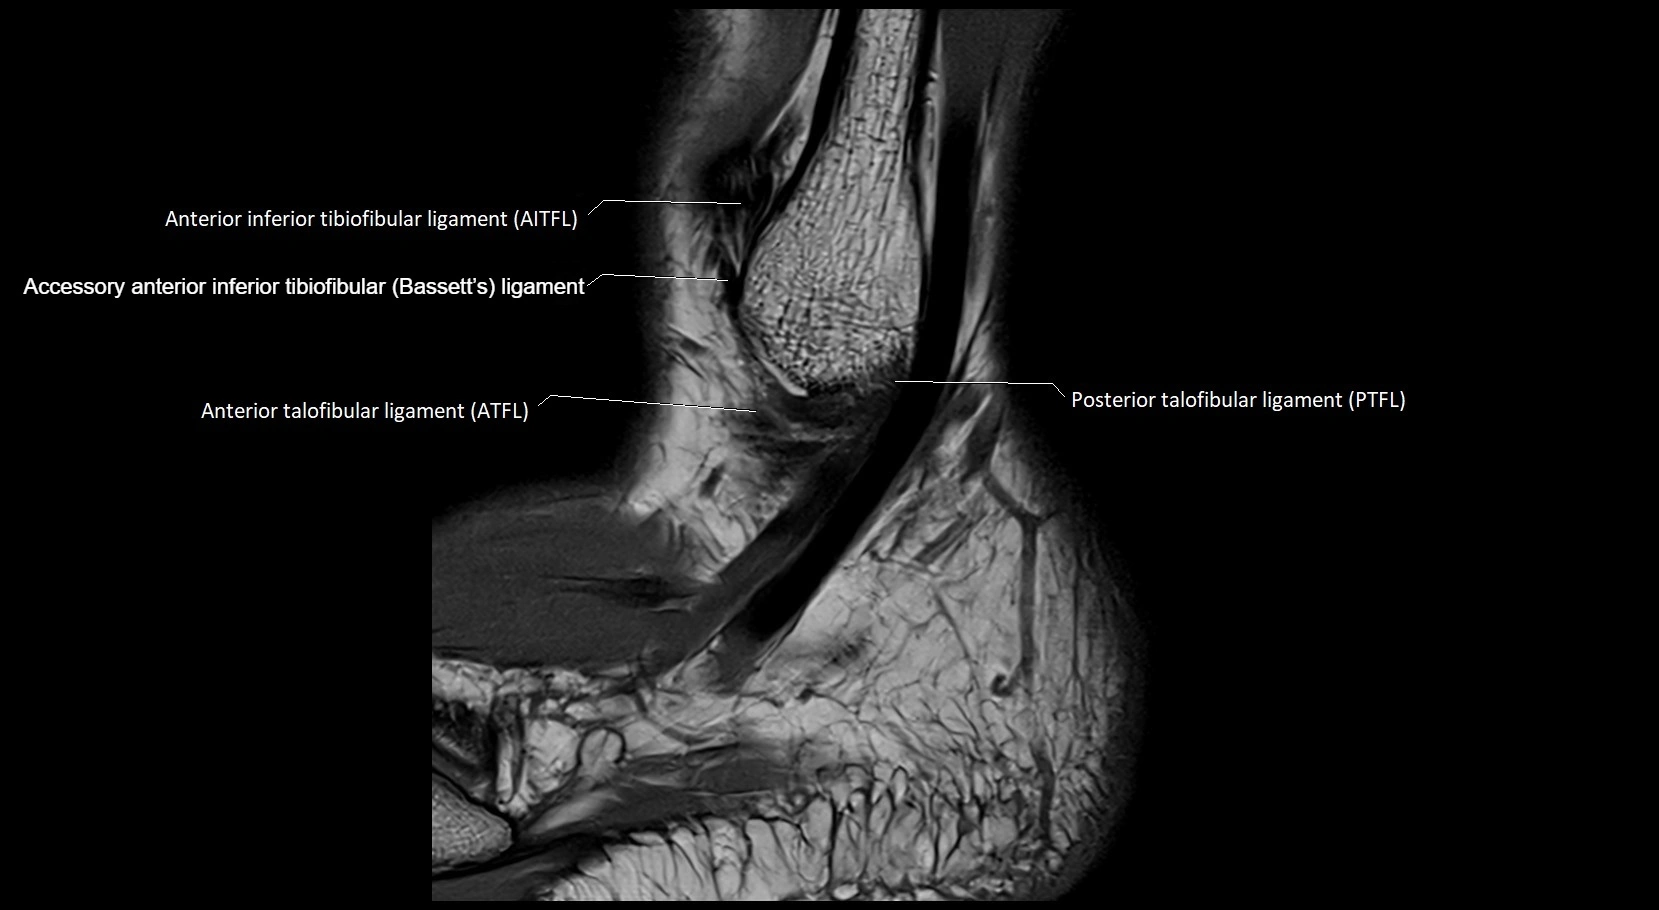

MRI image

image